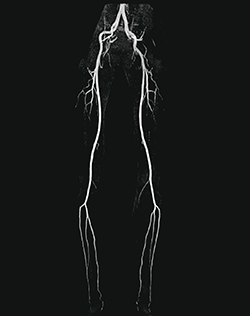

症例5:非造影下肢MRA(QISS)

E11には,心臓領域における機能として,呼吸による心臓の位置ズレを自動補正する“HeartFreeze”も搭載している。加えて,末梢血管描出を高速に行うために開発された新しい非造影MRA技術“QISS”が搭載された。QISSは,従来よりも大幅に撮像時間を短縮し、10分程度で下肢全長の撮像が可能であり,かつ再現性の高い撮像法でもある。このほかにも,人工関節などのインプラントによるメタルアーチファクトを軽減する“syngo WARP”といった,整形領域での検査に対応したアプリケーションも採用されている。